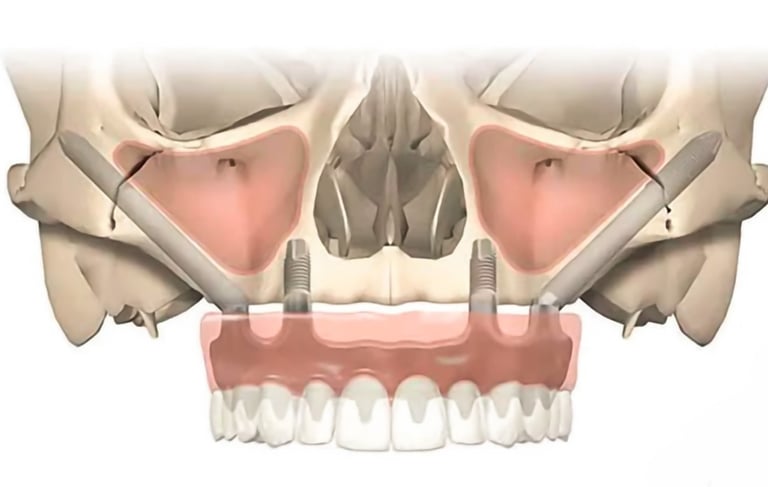

Son implantes largos que se anclan en el hueso cigomático (pómulo) en lugar del maxilar, utilizados en pacientes con severa pérdida ósea en la mandíbula superior.

Colocación de implantes cigomáticos

Es un procedimiento para añadir hueso a al maxilar superior en la zona de los molares y premolares, elevando el suelo del seno maxilar para permitir la colocación de implantes.

Elevación del Seno Maxilar